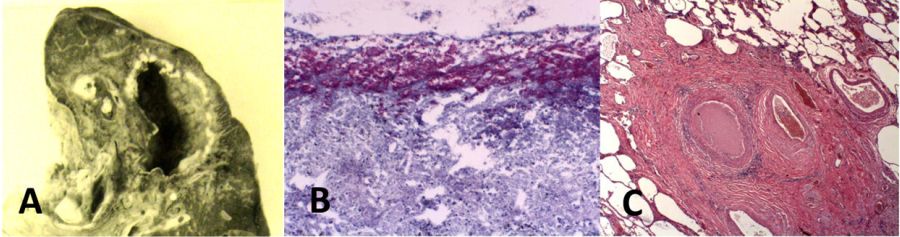

人与动物牛结核病病理

由于目前对原发性后结核病的许多认识是基于对家兔牛分枝杆菌的研究,我们试图研究牛结核病在人和动物身上的病理学。我们发现发表的文章很少。通过巴氏消毒牛奶和动物皮肤试验来预防牛分枝杆菌感染降低了人们对该病的兴趣和研究组织的可获得性,而在抗生素引入半个世纪之前,这两种方法也降低了人们对MTB的兴趣。最近的出版物只描述了最轻微的疾病。然而,Creighton和后来的Francis描述了牛结核病在牛和人类身上的病理。这种病在牛身上被称为珍珠病,因为病变除了在肺、淋巴结和其他器官内外,还在胸膜和隔膜表面形成直径达2cm的不连续结节(珍珠),如图9所示。组织学上为典型的干酪样肉芽肿。这些病变通过软化和侵蚀支气管和其他结构形成小的空洞。多个病变可以合并形成更大的空洞。在感染牛结核病的人和牛身上也观察到类似的病理结果。早在1821年,Laennec就将其描述为一种独特的病理模式。在他1882年的Gulstonian讲座中,Ewart发现了一组结核病例与他描述的“色素性纤维瘤结节的束状肿块”相似。空洞较小,在葡萄状结节内形成。有时,多个结节融合产生较大的空洞。最近在野生动物身上对牛结核病的研究显示,多个小结节类似珍珠或葡萄串,中央坏死产生空洞。牛分枝杆菌确实会引起支气管内感染和结核性肺炎,但这些不会对空洞的形成产生实质性的影响。这些描述与目前牛分枝杆菌感染兔空洞形成概念下的的病理非常相似,图9。所有可获得的信息都与下述概念一致:干酪样肉芽肿的侵蚀形成空洞是对牛分枝杆菌形成空洞的准确描述,而不是对结核分枝杆菌形成空洞的准确描述。

图9. 牛分枝杆菌在人类和动物身上的病理学。牛分枝杆菌的典型病变是直径达2厘米的结节,生长在浆膜表面,包括隔膜、肺和腹膜,以及器官深处。最上面的两个图显示了一个人(a)和一个野牛(B)的胸膜表面的病变。下图为人类(C)和兔(D)肺腔病变切面。空腔是干酪化的肉芽肿,它经历了中心软化和侵蚀到邻近结构中产生空洞。

牛分枝杆菌在人(E)兔(F)和野猪(G)体内引起的蛀牙具有相似的特征。干酪样肉芽肿已侵蚀入支气管。兔和野猪病变图像显示中央软化和液化。唯一可用的人类病变图像显示相似的形态。(H & E染色40倍放大)。